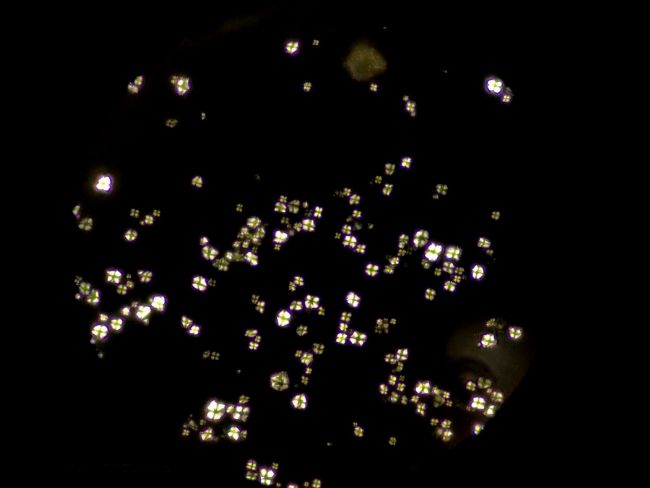

偏光下的中藥顆粒

偏光觀察是對結晶物質的形態進行觀察和測量的一種技術,在生物顯微鏡ML31基礎上加入偏光附件,即可升級為簡易偏光顯微鏡ML31-P,正交偏光下可以看到顆粒出現了偏光反應,形成以粒心為中心的黑色“十”字外觀,這是淀粉粒的典型特征。

在其他視野中,我們也看到了一些其他偏光反應,可能是草酸鈣簇晶之類成分,也可能是玻片或者水中的雜質。